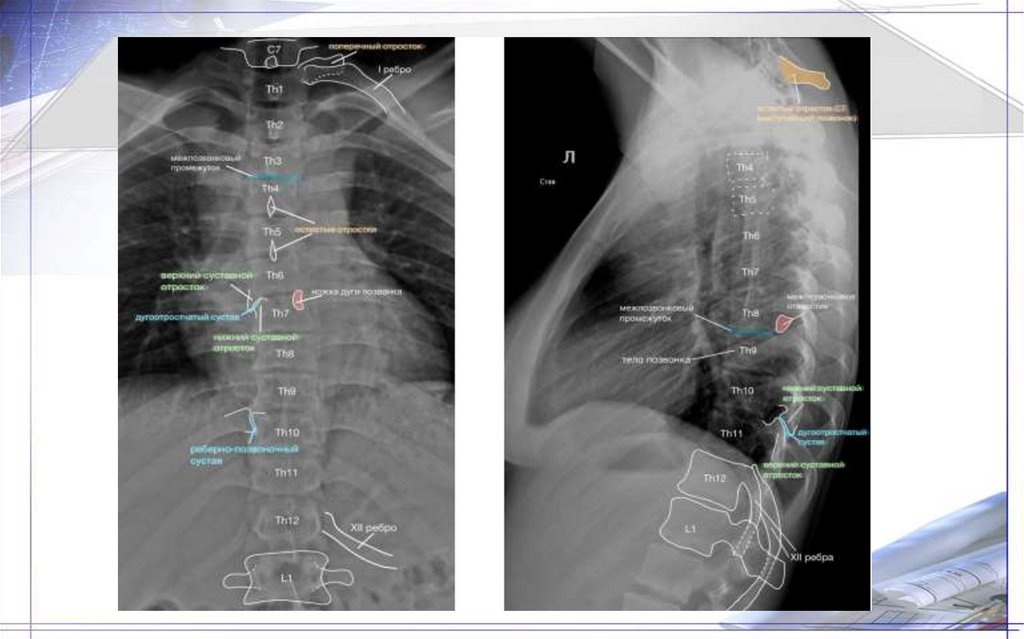

Грудные позвонки(12):

-тела позвонков выше и толще шейных

-размер тел позвонков увеличивается по направлению к поясничным

-на заднебоковой поверх-ти тел 2 фасетки(верхние и нижние реберные ямки)-2 позвонка образуют полную суставную ямку(место

сочленения с ребром)

-дуги образуют округлой формы позвоночные отверстия, но меньше, чем у шейных

-поперчн.отросток кнаружи и кзади и имеет небольшую реберную ямку поперечного отростка(сочленение с бугорком ребра)

- суст.поверх-ть суст.отростков во фронтальной плоскости: у верхн.суст.отростка направлен кзади, у нижнего-кпереди

-остистые отростки 3хгранные, длинные, остроконечные, обращены книзу.

- в среднем отделе грудных позвонков остистые отростки один над другим(в виде черепицы)

-нижние грудные позвонки по форме приближаются к поясничным